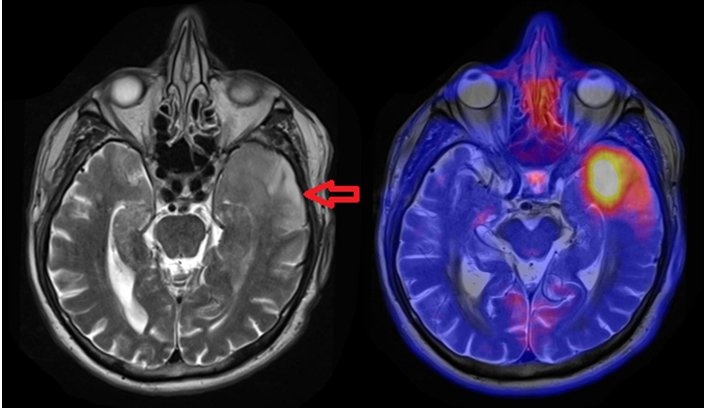

[11C]Methionin-Aminosäure-PET-MRT von Hirntumoren. Links: Leichte Schwellung im linken Temporallappen des Gehirns. Rechts: Die Region hat einen deutlich gesteigerten Aminosäurestoffwechsel („Aufleuchten") als Zeichen eines bösartigen Tumors.